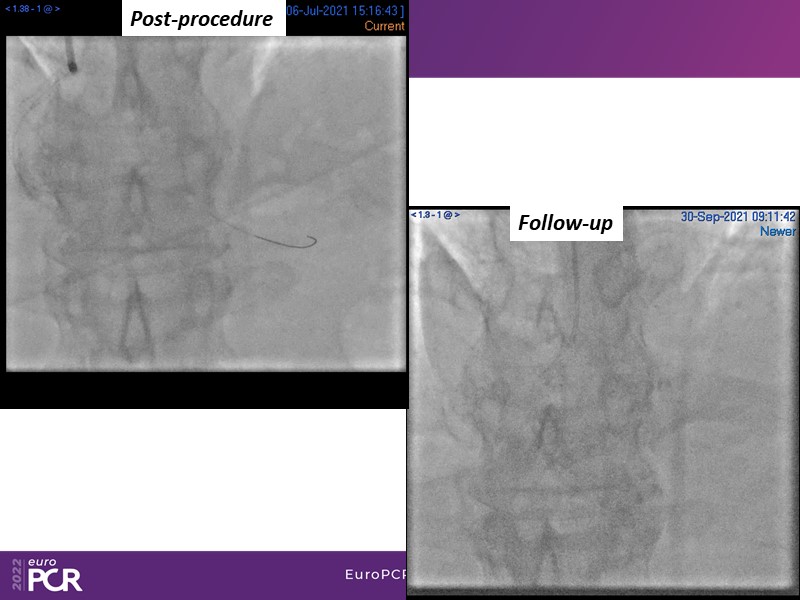

- To find out more about the application and mechanism of a sirolimus coated balloon for coronary artery disease treatment with case presentations in complex settings